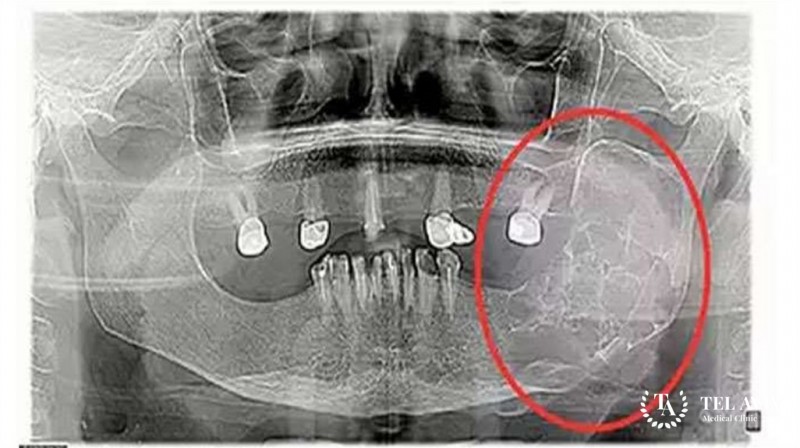

- Цифровая рентгенография костей. Современные цифровые рентген-установки позволяют хорошо визуализировать опухоль и определить характерные для остеобластокластомы признаки.

- Компьютерная томография (КТ) и магнитно-резонансная томография (МРТ) – это современные методики визуализации опухолей костей. Четкие послойные снимки очага интереса позволяют не только установить диагноз, но и помогают выбрать оптимальный вариант хирургического вмешательства и спланировать его в мельчайших деталях.